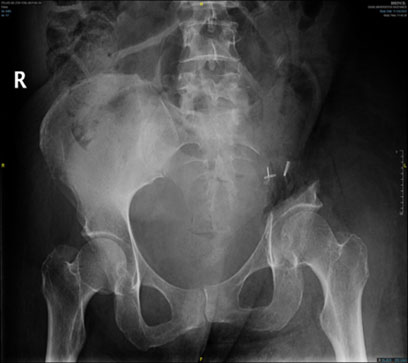

Ameliyat sonrası: Röntgende ol sakroiliak rezeksiyon görülmekte